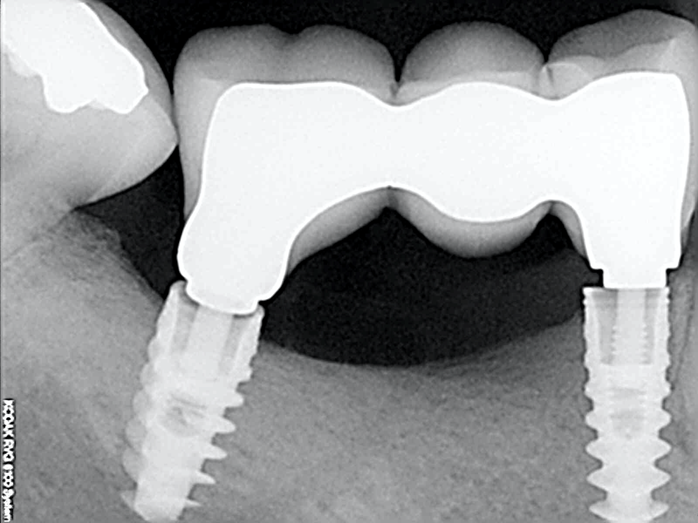

Рис. 15 Работа с уровня имплантата с имплантатами с внутренним соединением осложняется отсутствием параллельности соседних зубов

Множественные имплантаты редко располагаются параллельно, что затрудняет использование супраструктуры для имплантатов, установленных на уровне кости. Обычно абатменты размещаются ниже уровня мягких тканей, к ним трудно получить доступ. Существуют винтовые и мостовидные абатменты, которые можно использовать на уровне имплантата, но их использование может способствовать смещению костного гребня и потере кости.

При множественной имплантации рекомендуется выбирать абатменты со следующи ми свойствами:

- Легкий доступ к абатменту, простота ортопедического протокола

- Винтовая или гибритдная цементно-винтовая фиксация

- Исправление проблем соосности при помощи угловых абатментов

Абатменты должны быть выбраны до того, как будут сделаны оттиски или внутриротовое сканирование для изготовления окончательного протеза. Соединять абатменты на слепке, сделанном с уровня имплантата и только потом изготавливать протез неправильно. Большинство систем имплантатов имеют абатменты, разработанные с учетом вышеперечисленных преимуществ, в основном известные как абатменты с несколькими базами, абатменты с несколькими единицами, трансформируемые абатменты, абатменты с винтовой фиксацией, конические абатменты, универсальные абатменты и другие.